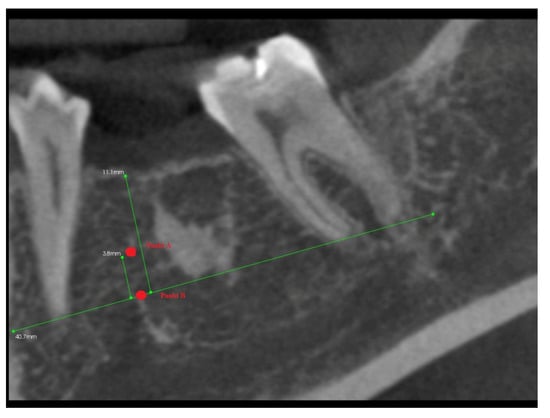

- The A line drawn through the apexes of the teeth adjacent to the post-extraction socket;

- The IC line drawn through the top of the buccal cusps of the teeth adjacent to the pos-extraction socket;

- The midline of the post-extraction socket (alveolus).

- Point (A)

- 1/3 of the distance between the A line and the IC line following the midline;

- Point (B)

- At the intersection of the midline and the A line.

3.2. The Results of Mean Values of the Alveolar Process Width and Height Measurements Performed after Tooth Extraction within the Space of 6 Months for Two Different Alveoli in the Same Patient

3.4. The Results of Mean Measurements of Height and Width of the Alveolar Processes of Two Extraction Sites (with and without PRF) in the Same Patient after 6 Months from Tooth Extraction Based on the Analysis of Volumetric Tomography